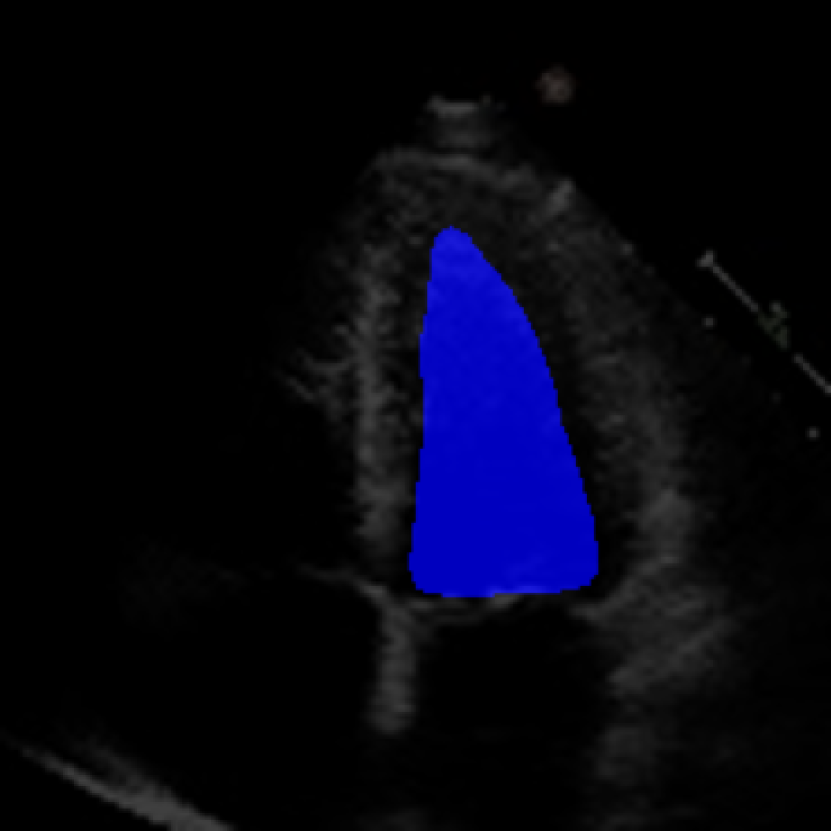

The 112x112 input is first resized to 299x299 as required by the Xception model. The Beat Extractor is then used to feed only whole beats to the LVEF estimation pipeline. A modified DeepLabV3+ model segments the left ventricle for every frame of the echocardiogram video (Figure LABEL:fig:segmentation). The area is measured, and a peak detector is then used to find the maximum (diastole) and minimum area (systole). The frame numbers corresponding to these extrema are recorded, and the video is clipped into smaller videos that go from diastole to systole. These smaller videos are independently fed to the Xception based feature extractor.

The ConFormer model demonstrated high performance in the estimation of Left Ventricular Ejection Fraction (LVEF) from echocardiogram videos (Figure 2). The model achieved a mean absolute error of 6.57 in LVEF prediction, indicating a high level of accuracy in its estimations (Table I). Notably, ConFormer outperforms the full video assessment of LVEF by EchoNet-Dynamic, a significant achievement given the model’s efficiency. With just 5.82 million parameters, ConFormer is significantly more efficient than existing models, making it a practical tool for real-world applications.